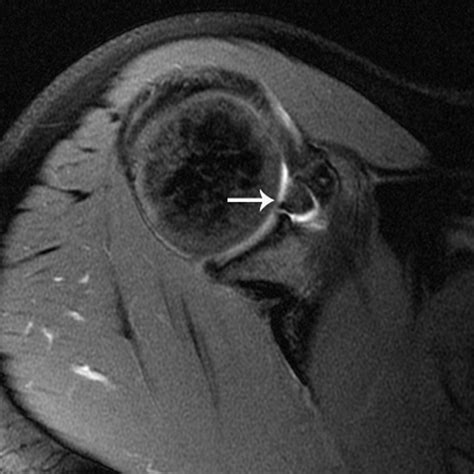

Interpreting the results of a Slap Tear MRI involves a thorough examination of the images by a radiologist. Key findings that indicate a SLAP tear include:

• Abnormal signal intensity within the labrum, suggesting a tear.

• Displacement or detachment of the labrum from the glenoid.

• Fluid or contrast agent extending into the tear, highlighting the extent of the injury.

• Associated injuries, such as rotator cuff tears or biceps tendon pathology.

Radiologists use specific criteria to classify SLAP tears based on their appearance on MRI images. For example, a Type II SLAP tear may show detachment of the labrum and biceps tendon from the glenoid, while a Type IV tear may exhibit a displaced flap of tissue.